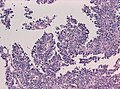

Papillary meningioma

Microscopic:

- discohesive meningothelial tumour cells around a fibrovascular core.

- perivascular pseudorosettes.